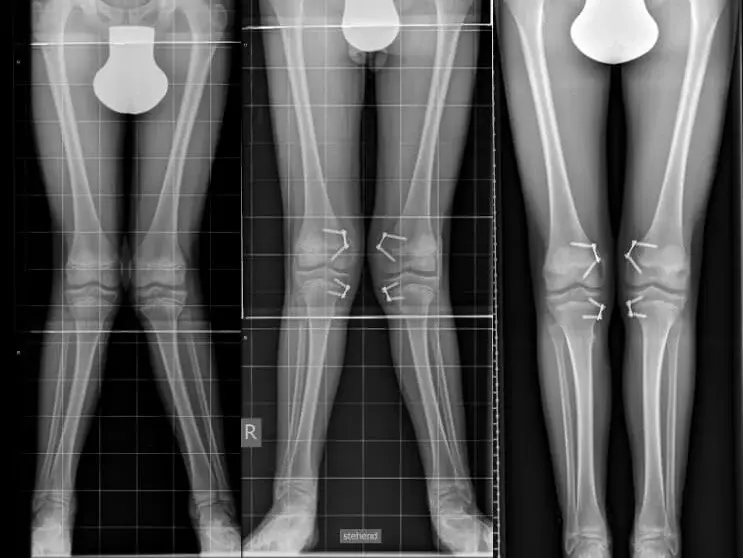

Das Bild zeigt ein Beispiel einer Achskorrektur mittel figure of eight Platten.